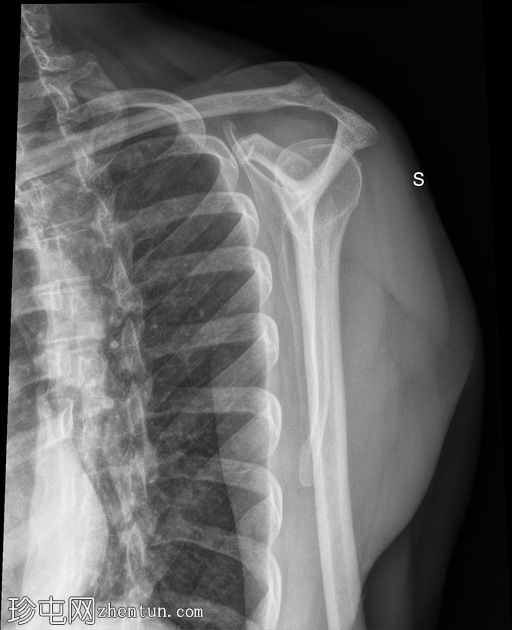

正位 -

外旋位

可见肱骨头周围、三角肌腱和冈上肌腱之间有钙化沉积物,呈致密均匀的阴影。